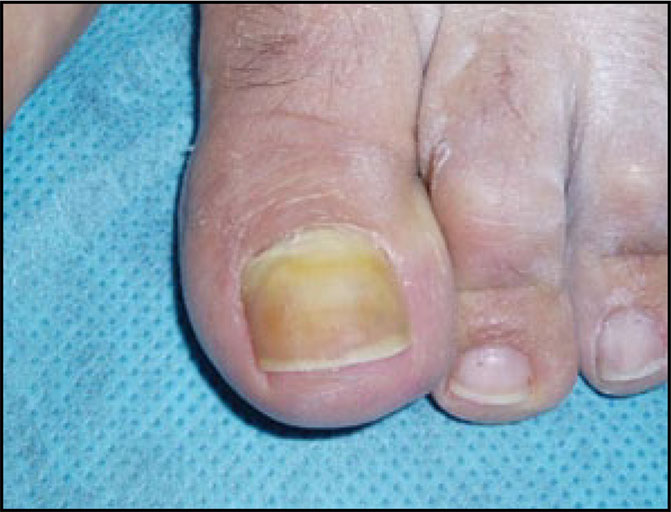

20. Prose NS, Abson KG, Scher RK. Disorders of nails and hair associated with human immunodeficiency virus infection. Int J Dermatol. 1992:32;453-7.

21. Gupta AK, Taborda P, Taborda V, Gilmour J, Rachlis A, Salit I, et al. Epidemiology and prevalence of onychomychosis in HIV positive individuals. Int J Dermatol. 2000;39:746-53.

22. Herranz P, García J, De Lucas R, González J, Pena JM, Díaz R, et al. toenail onychomycosis in patients with acquired immune deficiency syndrome: treatment with terbinafine. Br J Dermatol. 1997;137:577-80.

24. Surjushe A, Kamath R, Oberai C, Sapple D, Thakre M, Dharmshale S, et al. A clinical and mycological study of onychomychosis in HIV infection. Indian J Dermatol Leprol Veneorol. 2007;73:397-401.